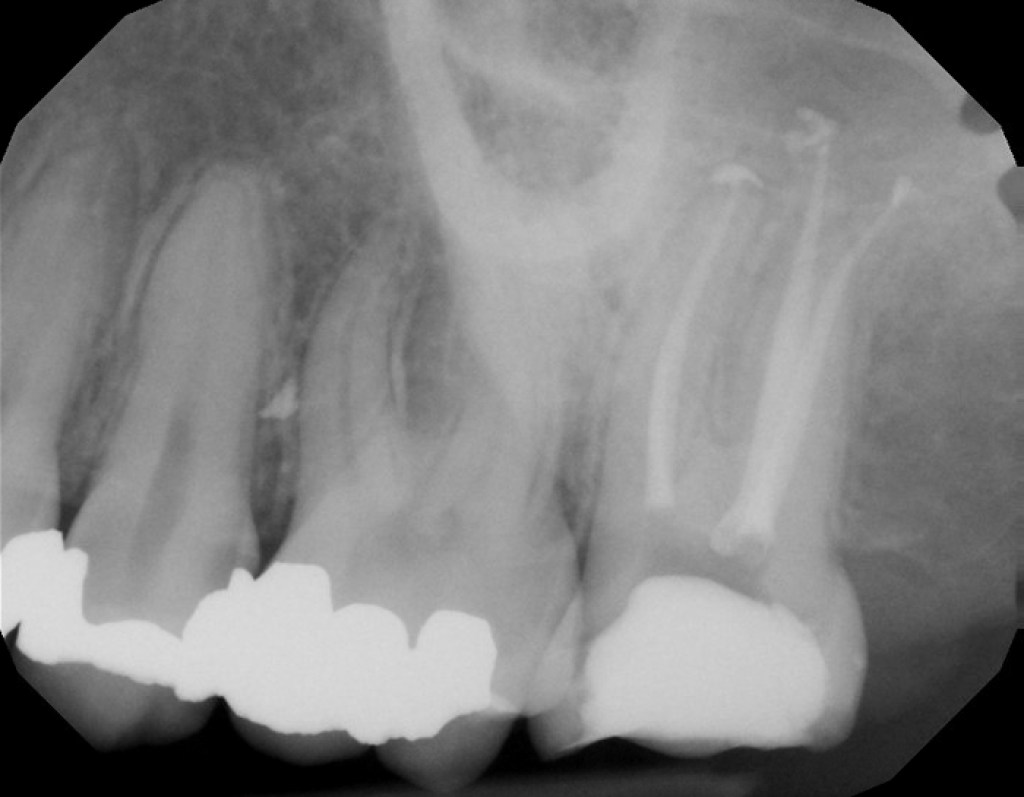

#18 NS-RCT

Dx: Asymptomatic Irreversible Pulpitis with NAT

Dx: SIP with SAP